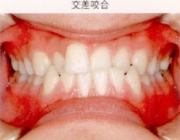

●交差咬合

下あごが左右どちらかにずれて噛んでいる場合を言い、臼歯の萌出方向が正しくないためや、片側噛み、頬杖 などの不良習癖によって起こります。